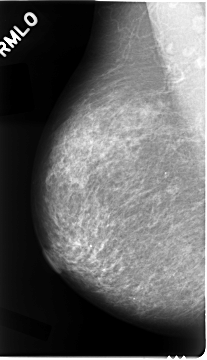

C_0023_1.RIGHT_MLO

RIGHT_MLO LINES 4680 PIXELS_PER_LINE 2680 BITS_PER_PIXEL 12 RESOLUTION 50 NON_OVERLAY